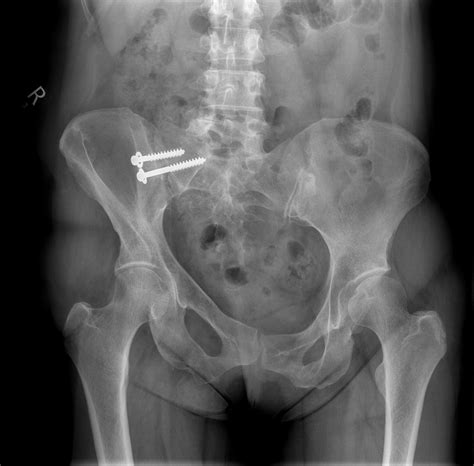

For severe cases of SI joint dysfunction that do not respond to conservative treatments, surgical intervention may be necessary. Surgical options include:

• SI joint fusion, which involves fusing the joint to eliminate movement and reduce pain

• Ligament repair or reconstruction to stabilize the joint

It is essential to discuss the potential benefits and risks of surgical intervention with a healthcare professional to determine the best course of treatment.